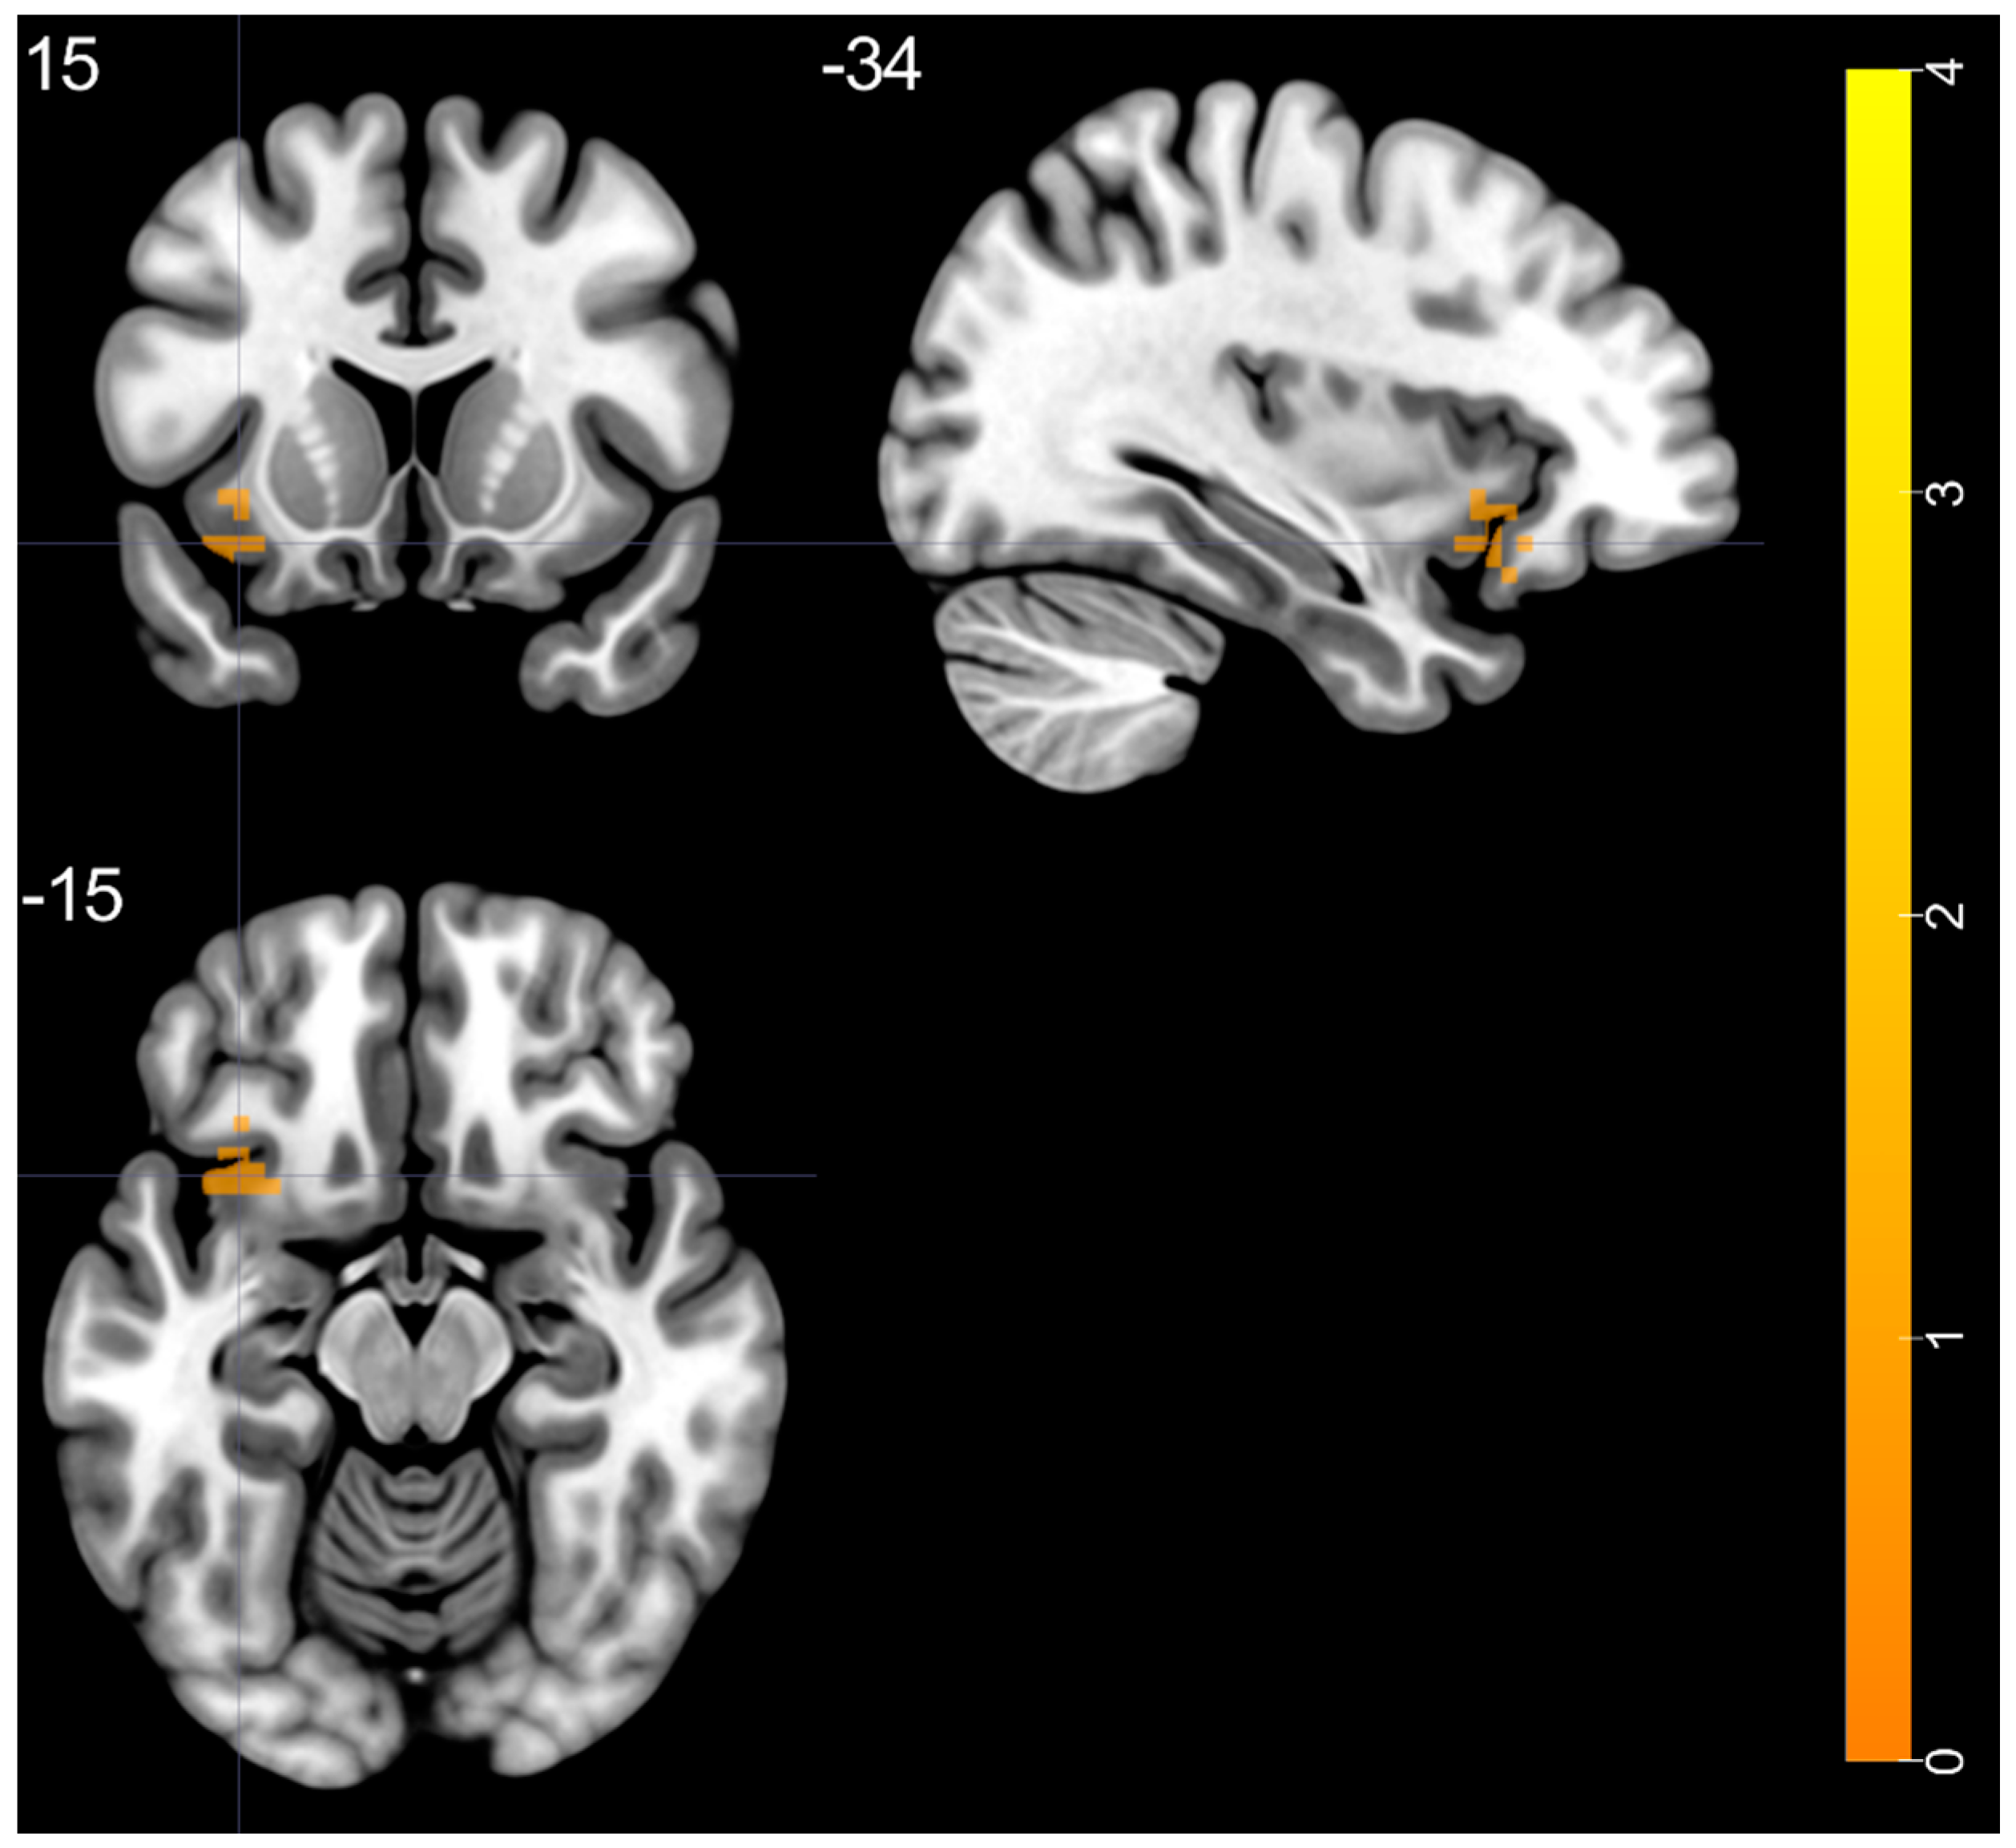

3.3. Typical ALFF Band: BD vs. HC

| Brain Regions | Peak T-Scores | MNI Coordinates | Cluster Size (Voxels) | ||

| BD > HC | |||||

| left insula—BA 47 | 4.228 | −36 | 15 | −15 | 37 |